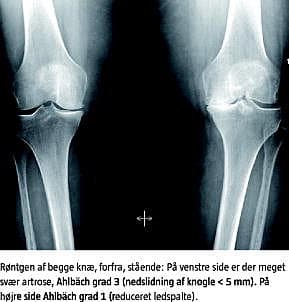

De radiologiske scoresystemer er baseret på røntgenundersøgelse i to planer, mens patienten står op, idet ledspalteforsnævring ofte kun kan påvises i stående stilling. Det er velkendt, at røntgenfund ofte ikke er i overensstemmelse med symptomatologien og de kliniske fund, og at man ved røntgenundersøgelse ikke kan påvise tidlige forandringer i brusk og mindre ændringer over tid [10]. Endvidere er graduering af brusklæsionernes sværhedsgrad på basis af røntgenundersøgelse usikker, især pga. lav specificitet og lav interobservatøroverensstemmelse [11]. I Skandinavien har der været tradition for at bruge Ahlbäcks graduering fra 1968 [12], hvorimod Kellgren-Lawrences graduering [10] bruges mest uden for Skandinavien (Tabel 2 ).